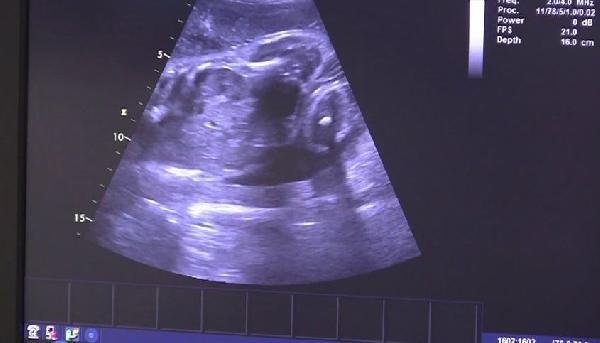

Nisan ayında hastaneye kaldırılan Eva’nın karnındaki fetüs, yaklaşık 300 gram ağırlığındaydı. Brno Üniversite Hastanesi’ndeki doktorlar, hastanede makinelere bağlı olarak 3,5 ay geçiren Eva’yı ameliyathaneye aldı.

21 Nisan günü Vojtech, eve geldiğinde eşi Eva’yı bilincini kaybetmiş şekilde buldu. Helikopterle hastaneye kaldırılan Eva, bilinçsiz bir durumda, dolaşımı sabit tutularak ve vücut sıcaklığını azaltılarak, Resüsitasyon ve Yoğun Tıp Bölümü'ne alındı. Karnındaki fetüsün kalbinin de düzenli bir şekilde attığı tespit edildi.